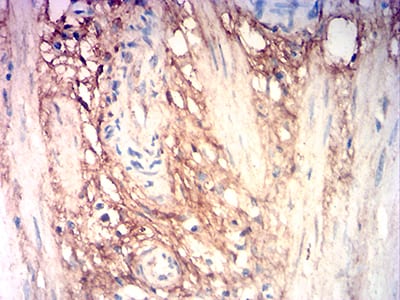

- Immunohistochemical analysis of paraffin-embedded human cervical cancer tissues using COL3A1 mouse mAb with DAB staining.

- Immunohistochemical analysis of paraffin-embedded human stomach cancer tissues using COL3A1 mouse mAb with DAB staining.